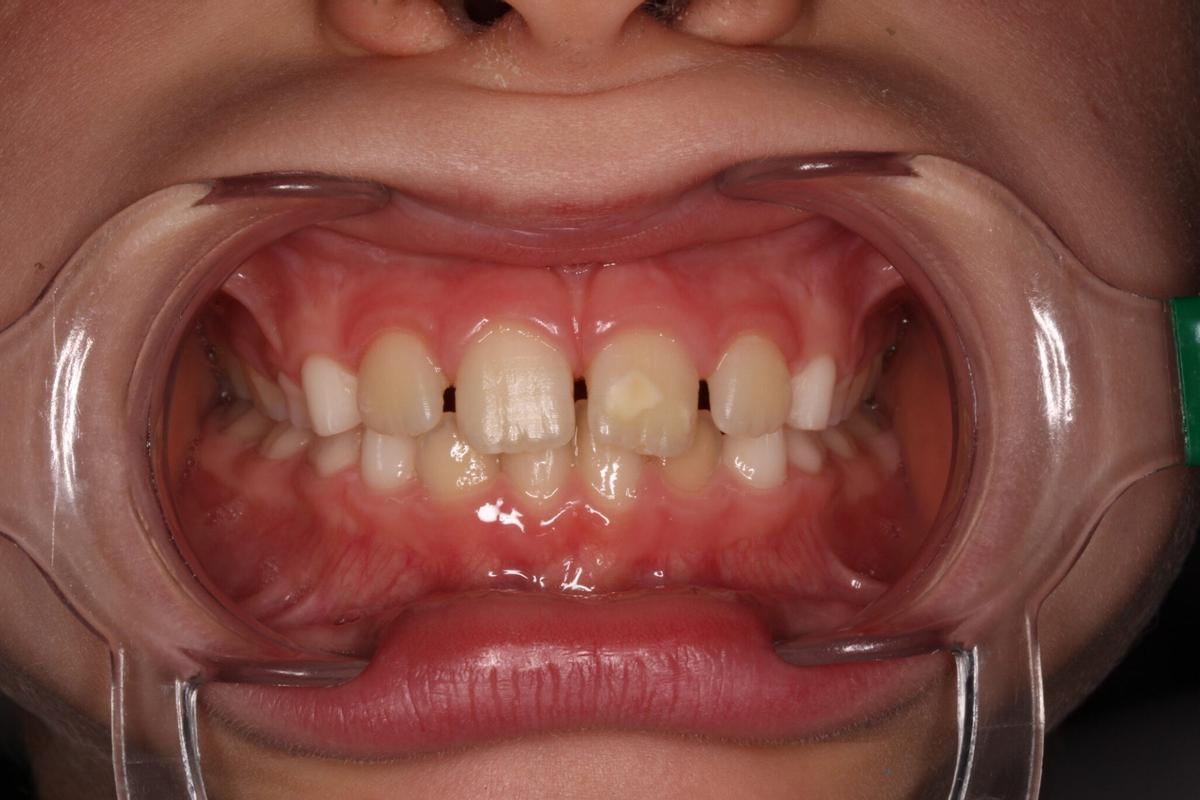

Primeramente, aclarar que el MIH se caracteriza por la presencia de manchas opacas blancas, amarillas y marrones, de aspecto mate, asimétricas, bien delimitadas y con alta porosidad. Esto refiere un primer y evidente problema a nivel estético que suele preocupar a los padres debido a que afecta a niños de 6 a 8 años y afecta al complejo y completo desarrollo de su autoestima, repercutiendo además directamente en sus relaciones con otros niños en los colegios y otros centros.

El MIH se caracteriza por la presencia de manchas opacas blancas, amarillas y marrones,